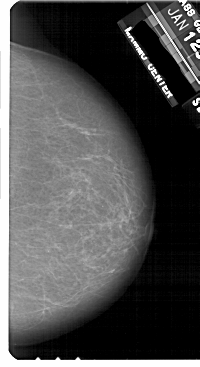

A_1812_1.RIGHT_MLO

RIGHT_MLO LINES 5206 PIXELS_PER_LINE 2746 BITS_PER_PIXEL 12 RESOLUTION 43.5 NON_OVERLAY